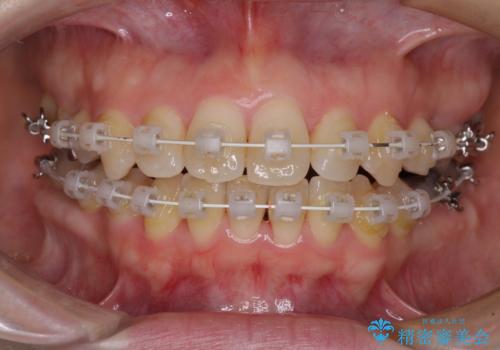

- 矯正装置

- 審美装置

むし歯となっている歯は状態が悪く、将来的に抜歯となる可能性が高かったため、定石で抜歯させる小臼歯の代わりにむし歯となっている大臼歯を抜歯し、ワイヤー装置にて矯正治療を行うこととしました。

イレギュラーな大臼歯抜歯矯正であったため、治療期間の長期化が想定されましたが、何とか3年ちょうどで終えることができました。